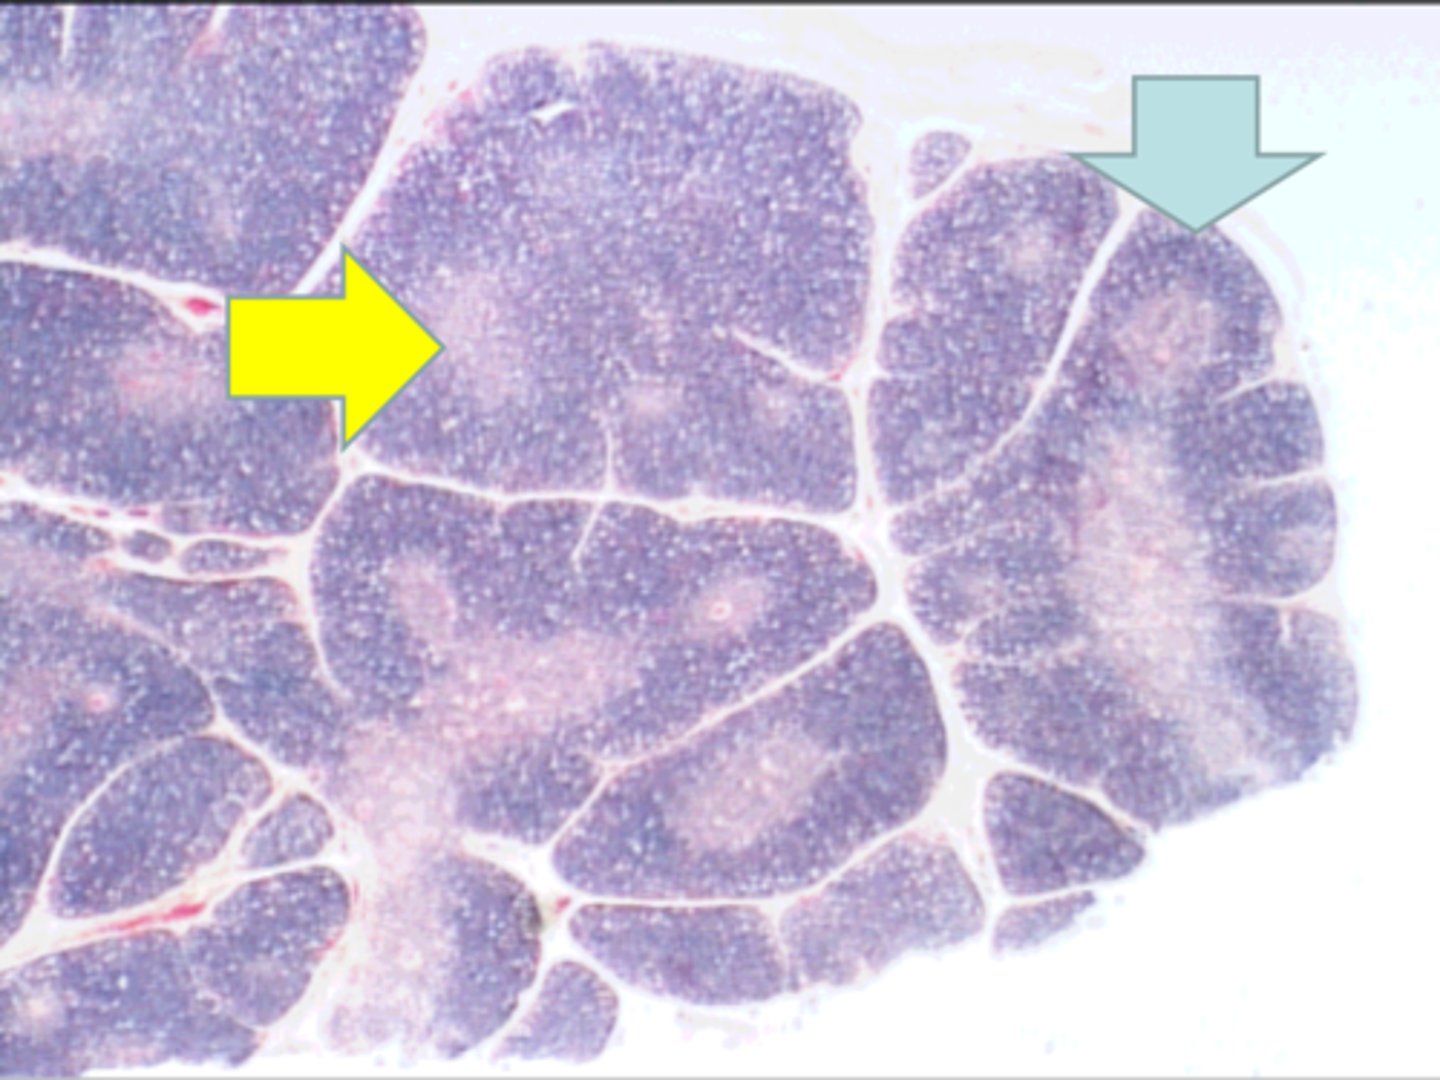

medulla

yellow arrow medulla

cortex

blue arrow cortex

thymus

where is this tissue? thymus

yellow arrow

medulla containing T lymphocytes

blue arrow medulla containing T lymphocytes

Hassall's corpuscle

red arrow Hassall's corpuscle

Where is this tissue located? thymus